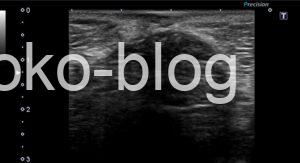

高周波プローブで確認してみよう!と

腹部用の設定ではないのでわかりづらいですが、腸管と連続しているように認めます。

腸管が皮下に見えるってことはヘルニアかな、カラーものらないから嵌頓の可能性もあるかなと医師に報告。